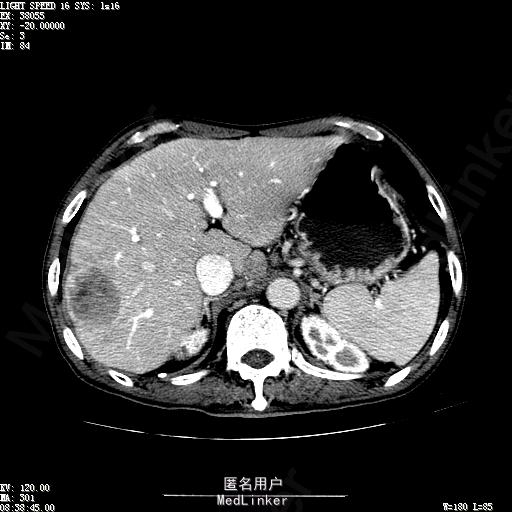

查体:体温36.3℃,脉搏76次/分,呼吸18次/分,血压120/80mmHg。神志清晰,肝病面容,皮肤粘膜颜色正常无黄染,全身皮肤未见皮疹、瘀点及紫癜,肝掌阳性,未见蜘蛛痣,浅表淋巴结未触及。巩膜无黄染,结膜正常。双肺呼吸音清,无胸膜摩擦音。心率:76次/分,心律齐,心音正常,无杂音,无心包摩擦音。腹平坦,无腹壁静脉曲张,未见胃肠型及蠕动波,双侧腹股沟可见手术瘢痕,脐部正常。触诊:无压及痛反跳痛,无腹肌紧张,无腹部包块。肝脾肋下未触及,Murphy征阴性,肾未触及,移动性浊音阴性。肝肾区叩击痛阴性,无脾区叩击痛。听诊:肠鸣音正常,4次/分,无气过水声。脊柱无侧弯,脊柱活动度正常,棘突正常,四肢正常,关节正常,无下肢水肿,无下肢静脉曲张,无杵状指趾。扑翼样震颤阴性。 门诊化验ALT9U/L,AST21U/L,HBVDNA<1.0E+03IU/mL,HBsAg1138IU/mL,WBC6.2x10^9/L,RBC3.92x10^12/L,PLT167x10^9/L,AFP28.95ng/ml,AFU 29U/L,彩超示肝右叶肝回声,大小约5.1*3.5cm,Fibroscan:脂肪变:163硬度10.8。 CT如下图

诊断:1、乙肝肝硬化 活动性 代偿期 原发性肝癌 2、胃溃疡 3、十二指肠球部溃疡 处理:血管介入治疗:手术者术前查看患者相关情况:化验回报:血细胞分析(五分类):*白细胞计数 8.1 10^9/L、*红细胞计数 4.00 10^12/L↓、*血小板计数 202.0 10^9/L、*血红蛋白 136 g/L,肝功酶谱:*丙氨酸氨基转移酶 5 U/L、天门冬氨酸氨基转移酶 22 U/L、*白蛋白 37.6 g/L、*总胆红素 17.8 umol/L,肾功能检测:*尿素 5.79 mmol/L、*肌酐 67.1 umol/L,凝血五项:凝血酶原时间 10.7 秒↓、凝血酶原百分活动度 93.3 %,甲胎蛋白测定:甲胎蛋白 30.30 ng/mL↑。患者病情平稳,今日术前准备,签署相关文件。 手术简要经过:患者平卧位,以右侧腹股沟区为中心常规消毒、铺巾、利多卡因局麻。改良Seldinger法逆行穿刺右侧股动脉成功,置入5F血管鞘。经血管鞘造影,见髂外动脉明显迂曲,经鞘送入超滑导丝,退出原5F血管鞘,换入5F长25厘米血管鞘。沿导丝送入肝管,将管头送入腹腔干,进一步送至肝右动脉。经正位、右前斜30°造影,明确肝右叶膈顶一处较大肿瘤染色,S5段一处较小肿瘤染色。以微导管超选S6段肝动脉干,经多角度造影明确为肿瘤供血动脉,注入混悬液(碘化油10毫升+雷替曲塞2毫克)3毫升,明胶海绵颗粒1/12支。再以微导管超选S7段肝动脉干,造影明确为肿瘤供血动脉,注入混悬液2毫升,明胶海绵颗粒1/20支。再以微导管超选S8段分支,造影明确为肿瘤供血动脉,注入混悬液2.8毫升,明胶海绵颗粒1/12支。再以微导管超选S5段肝动脉分支,造影明确为较小肿瘤供血动脉,注入混悬液0.8毫升,明胶海绵颗粒1/30支。退出微导管。经肝右动脉注入奥沙利铂100毫克。退出肝管。拔出血管鞘,局部压迫5分钟。加压包扎。